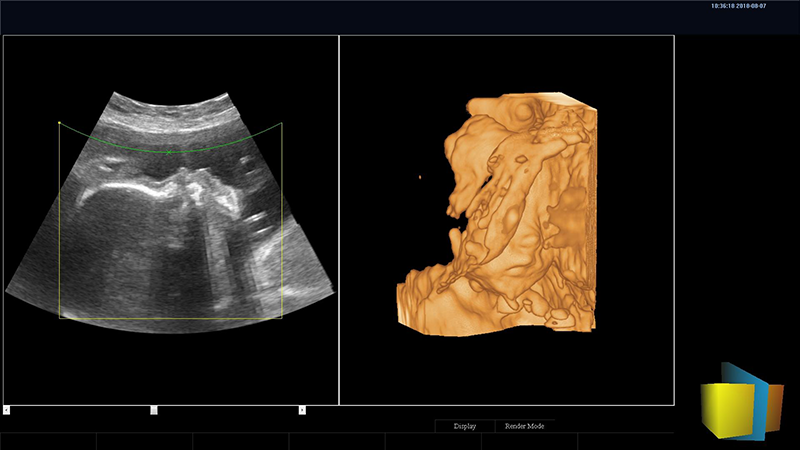

四維圖像